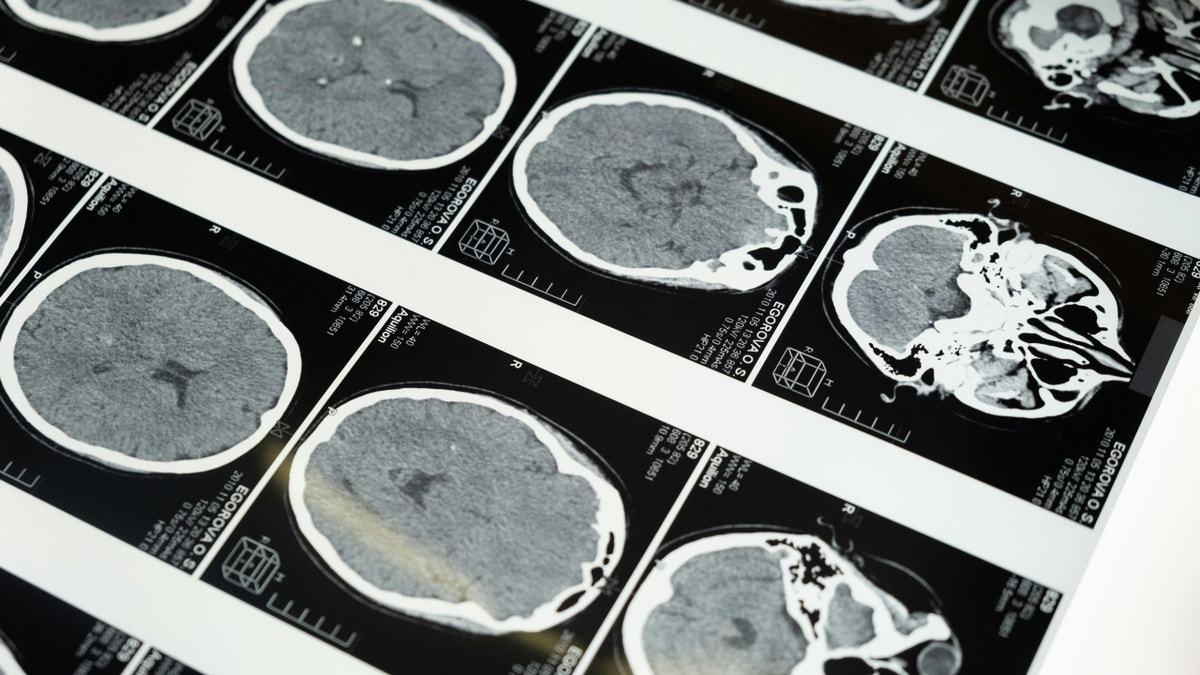

Brain imaging highlights the regions researchers study as companies explore noninvasive ultrasound brain-computer interface technology. (Kurt "CyberGuy" Knutsson)